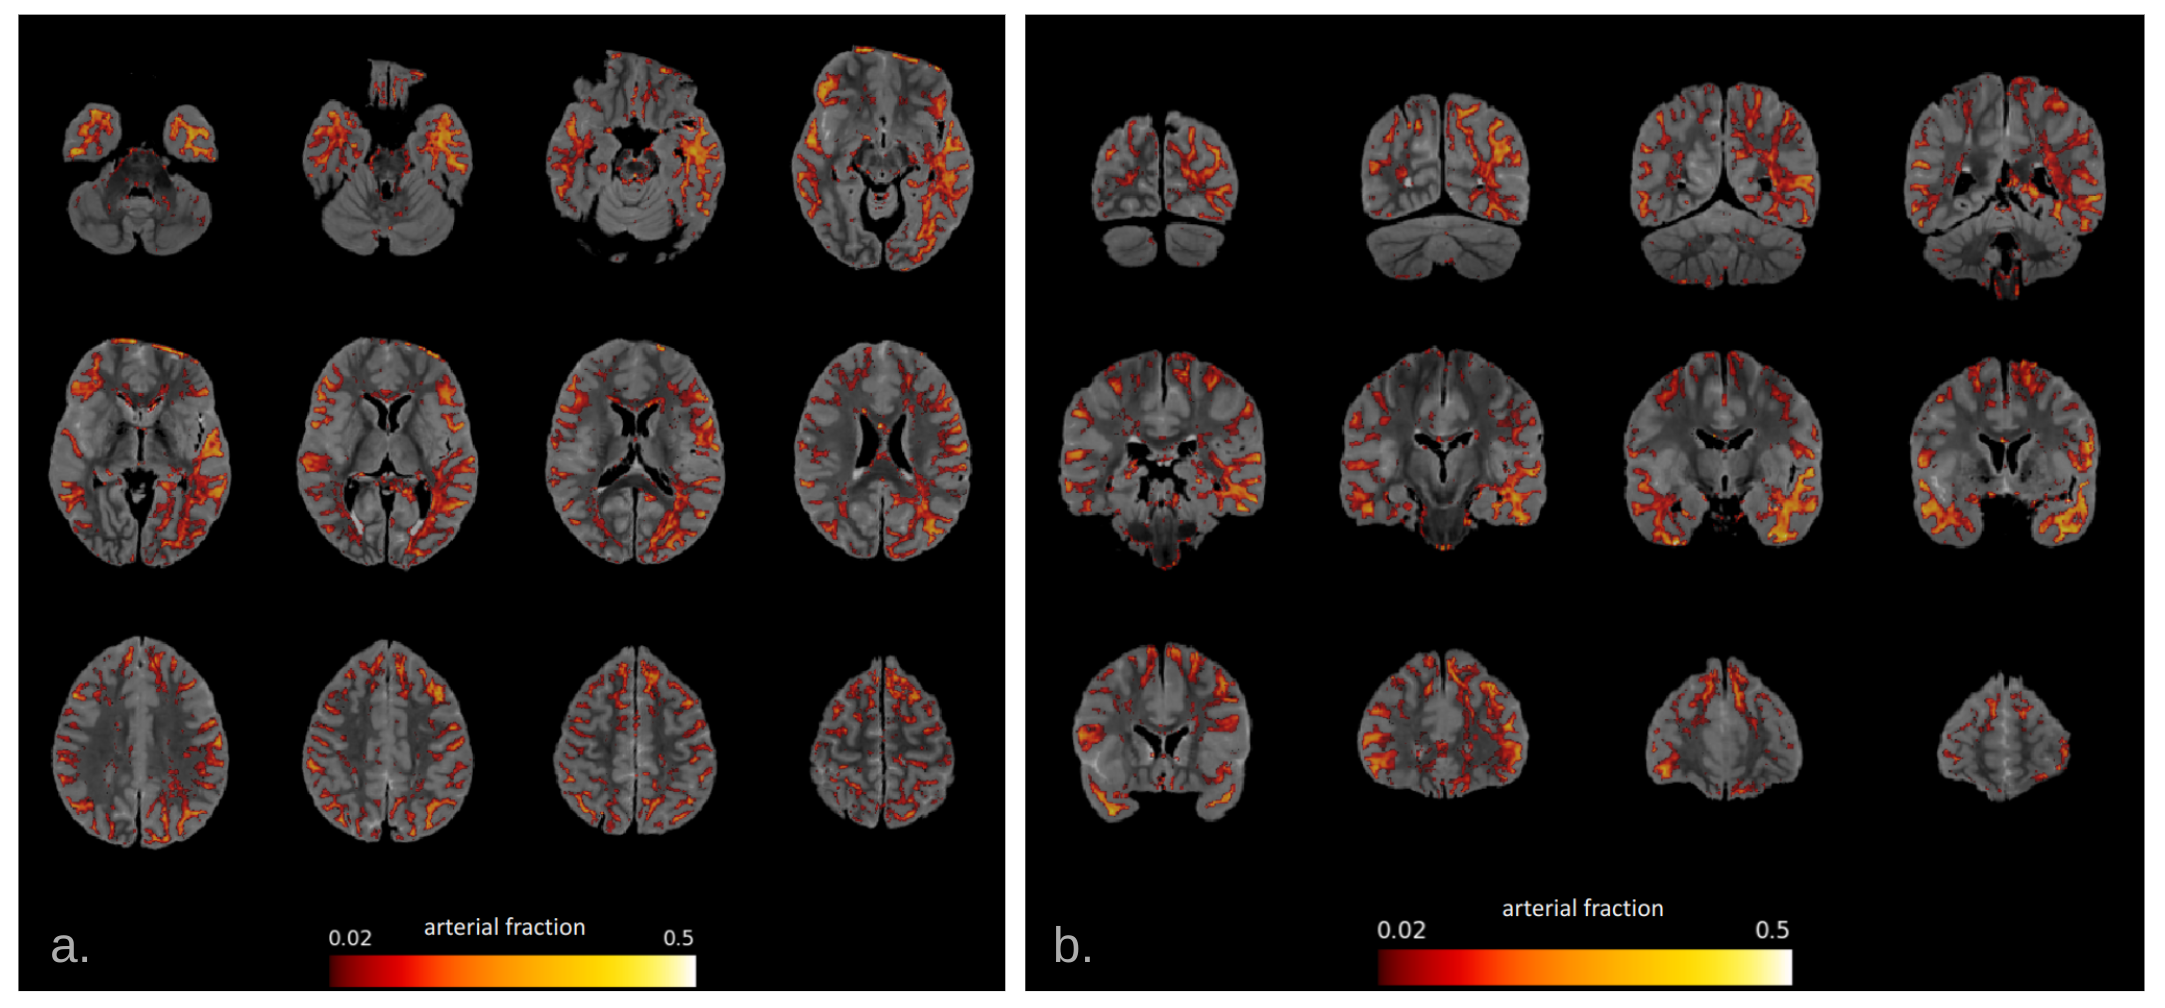

Fig.1 illustrates the preparation and post-processing pipeline from the gelatin injection step till the projection of MCA volume contribution for each deep WM bundle. Fig.2 depicts axial and coronal slices of the MCA volume fraction map overlaid onto the corresponding proton density map computed from the T2-weighted qMRI data. Fig.3 shows the statistical analysis highlighting the MCA contribution in the vascularization of deep WM bundles. Fig.4 illustrates the vascularization of the most MCA-irrigated deep WM bundles (arcuate, frontal aslants, inferior fronto-occipital, inferior/middle longitudinal, optic radiations, uncinate and ventral visual stream).

Figure 2: 1.2mm isotropic proton density-weighted axial (a) and coronal (b) sections of the MCA-injected brain overlaid with the inferred arterial volume fraction (threshold=0.02).